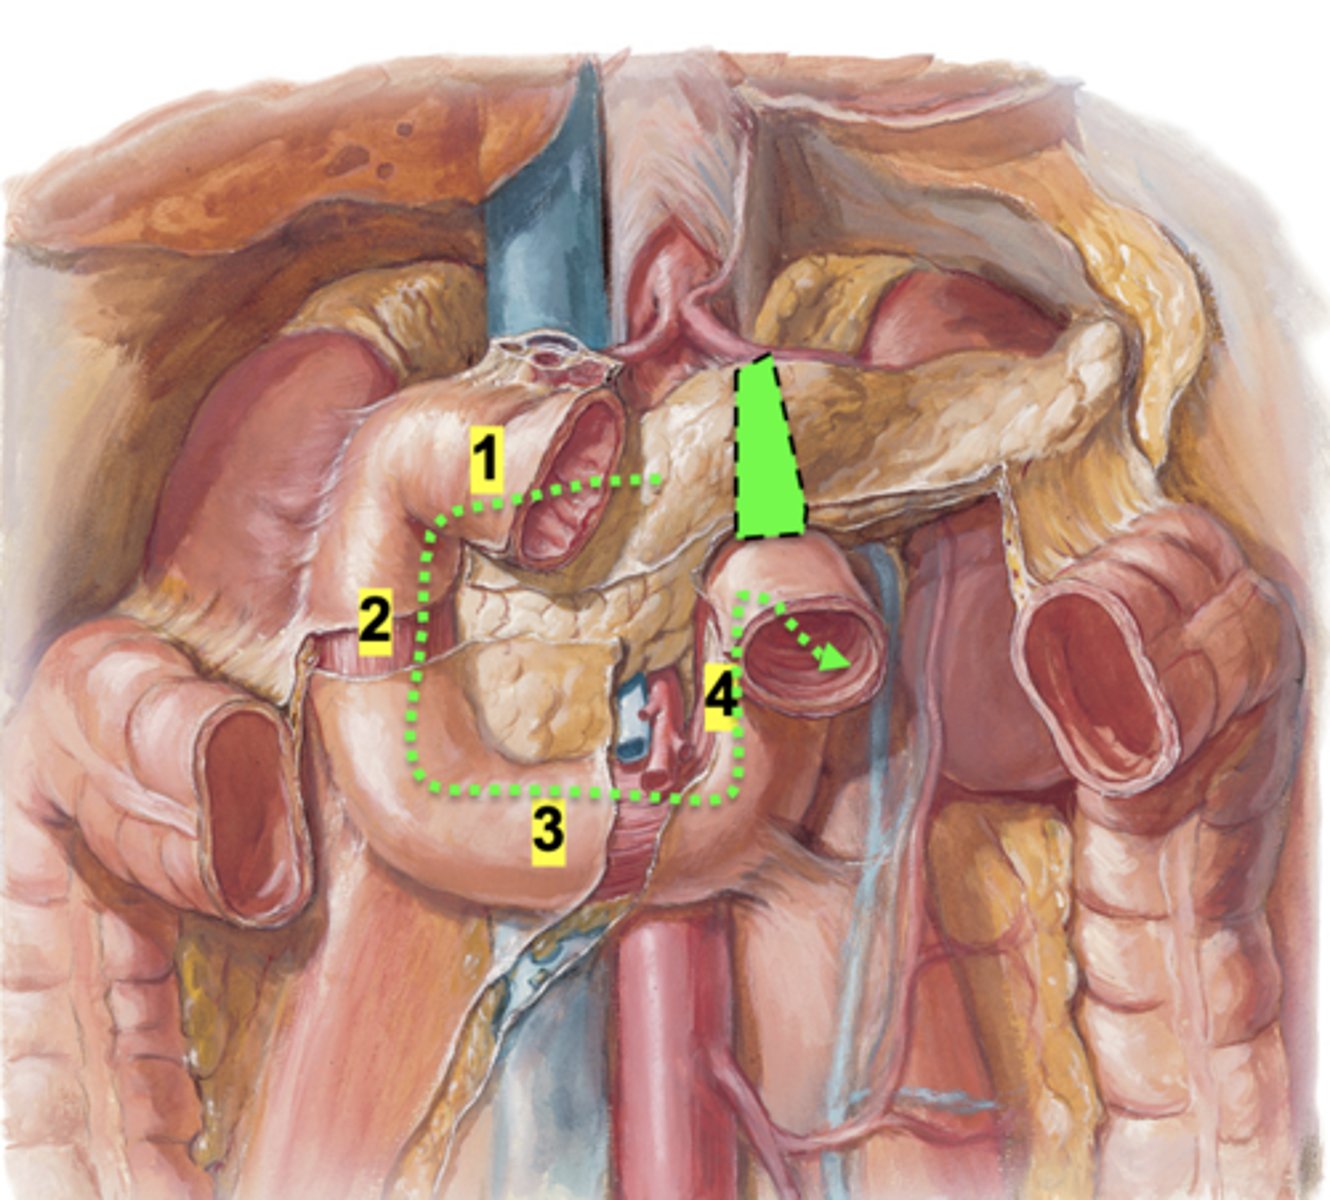

What are the four parts of the duodenum?

Superior (1st), descending (2nd), inferior (3rd), and ascending (4th) portions.

What is the ligament of trietz?

a thin band of tissue (peritoneum) that connects and supports the end of the duodenum (ascending part) and beginning of the jejunum in the small intestine.

It's also called the suspensory muscle of duodenum

What is the clinical importance of the ligament of trietz?

Injury before the ligament - GI blood appear dark, tarry stool (melena)

Injury after the ligament - GI blood appear bright red

How do you identify the duodenojejunal junction on imaging?

Located left of midline at ligament of Treitz where bowel becomes intraperitoneal jejunum.

Where do the pancreatic and bile ducts enter the duodenum?

They enter the second (descending) part of the duodenum at the major duodenal papilla

What is the accessory pancreatic duct?

smaller duct that empties directly into duodenum via minor duodenal papillae (NOTICE this is ONLY pancreatic juices NOT BILE)